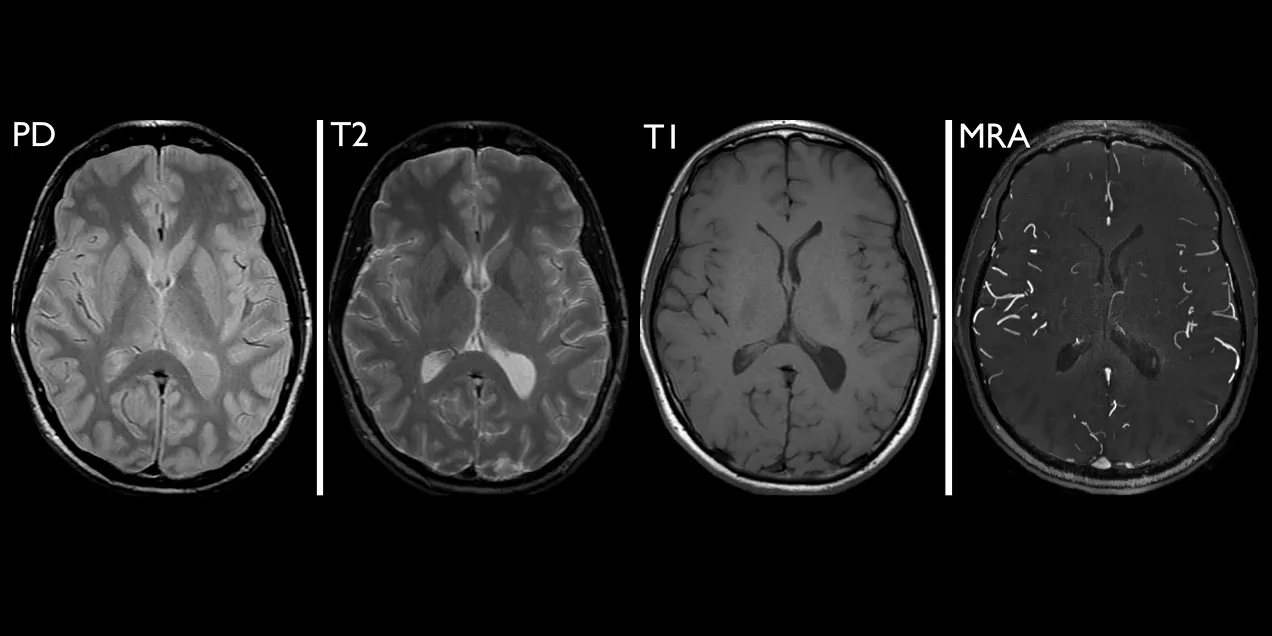

four axial brain images side by side showing PD, T2, T1, and MRA MRI sequences for comparison

Selected images from a brain MRI obtained in a normal volunteer, all acquired at the same level through the head. Proton density (PD, top left), T1-weighted (T1, bottom left), T2-weighted (T2, top right), and MR angiography (MRA, bottom right) scans have very different image contrast that reveals specific information about various structures in the brain.

Image intensity in MRI depends upon several parameters. These are proton density, which is determined by the relative concentration of water molecules, and T1, T2, and T2* relaxation, which reflect different features of the local environment of individual protons. The degree to which these parameters contribute to overall image intensity is controlled by the application and timing of radiofrequency energy through different pulse sequences.